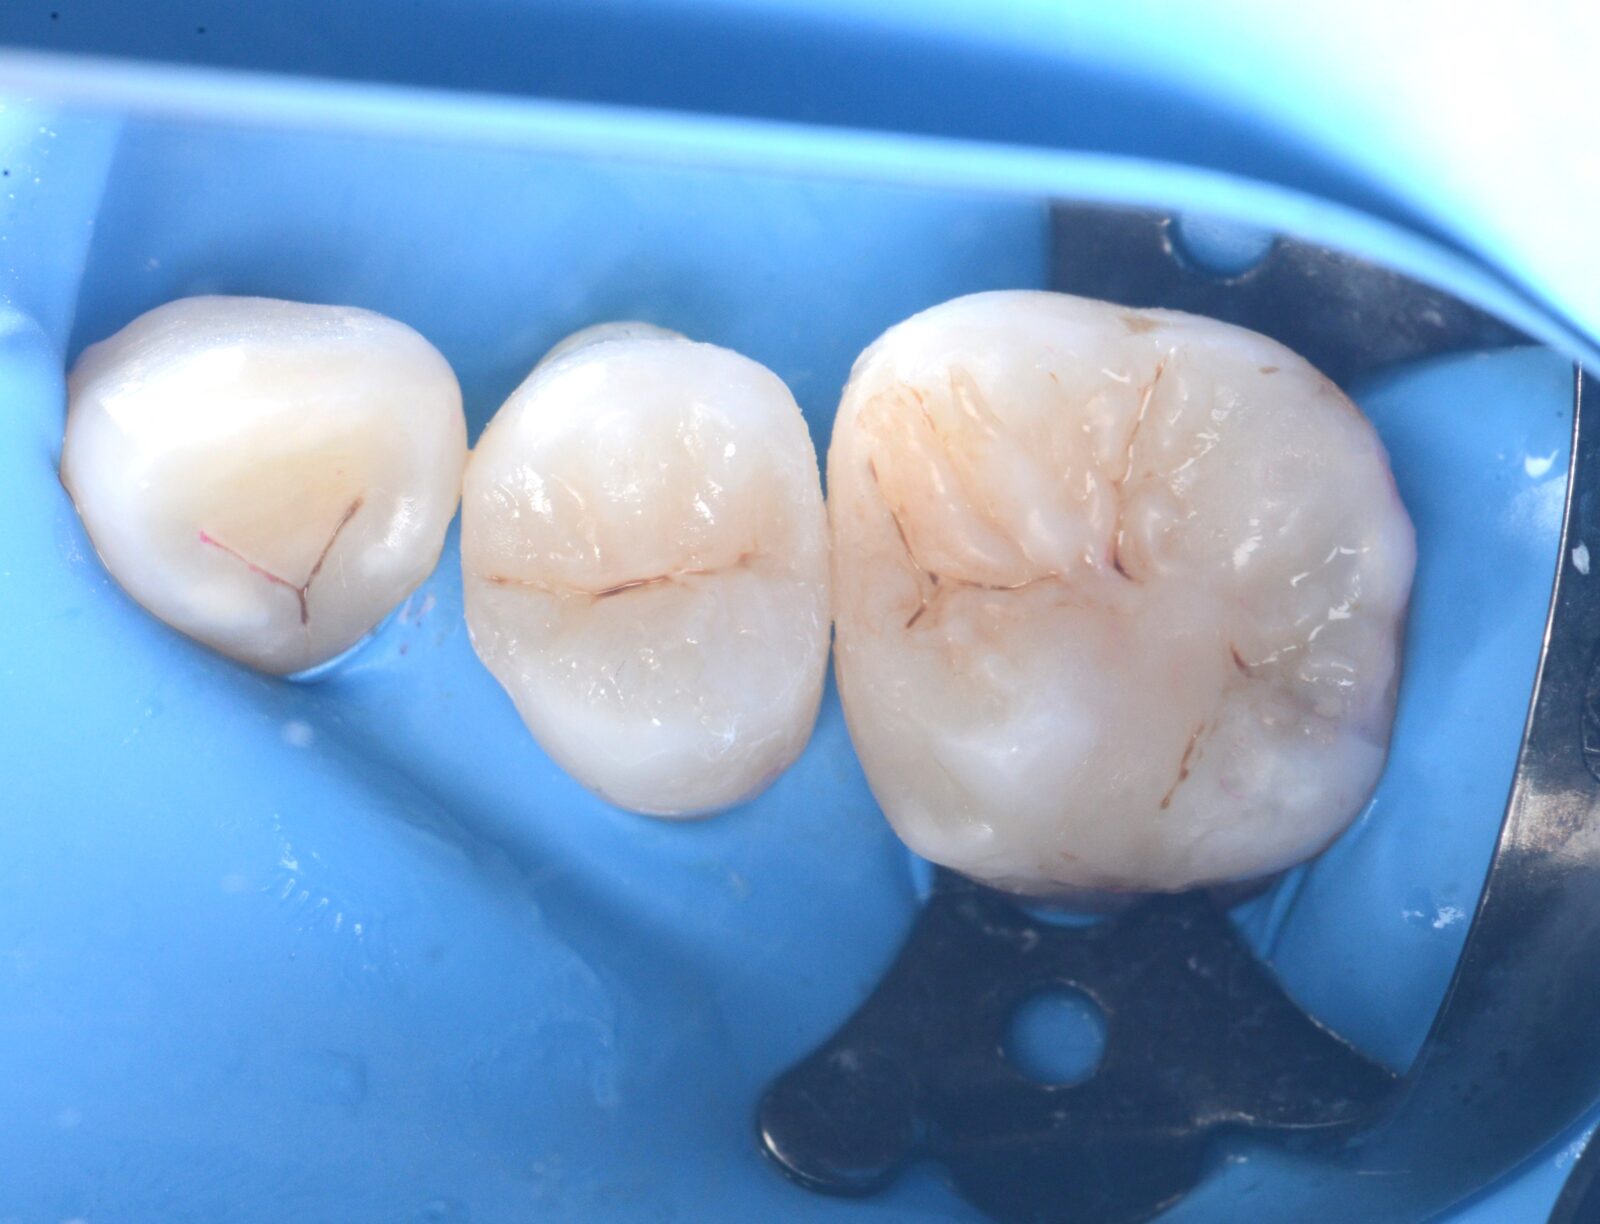

治療前 治療後

左上7ダイレクトボンディング

局所麻酔後に、古い詰め物を除去。   う蝕検知液で染色し、取り残しなく感染歯質を除去。   その後、ラバーダムを装着し、改めて取り残しがないかを確認。   見えている歯をプラークチェッカーで赤く染めて、表面の汚れを徹底的に清掃…